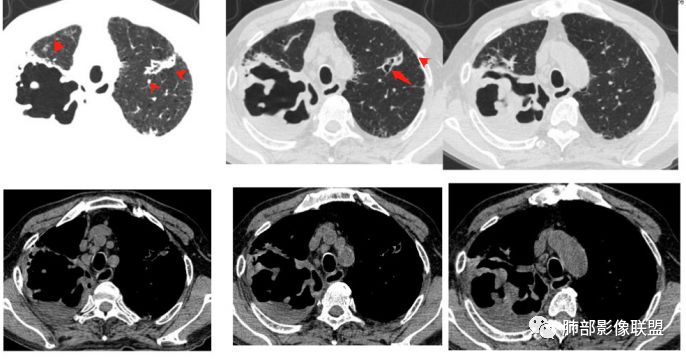

这些是坏死收缩形成的。空洞里面往往很干净,这个乳头凸起往往很光滑。毛霉是丝丝缕缕

曲霉,也只有慢性曲霉才会这样,急性形成不了这种光滑,必须是时间久,坏死彻底,有明显纤维化的修复才会如此。

初学者:这个毛霉,壁是毛毛的,不。。。空洞壁内部不光滑的,里面丝丝拉拉的

包括曲霉,急性期也是丝丝拉拉的,但是慢性期,坏死物排空才可能光滑赶紧,这个人没有咯血。。

毛霉因为嗜好血管,容易咯血,周围一般都是毛的。内壁也不会太光滑,里面也不会太干净

随着时间。。他会慢慢变,但是内部还是那种很纤细的条索。。一般不会有乳头状突起

1)空洞内坏死相对彻底(未见絮状物或丝状物等)。

2)空洞壁密实,内外壁都清楚,这是慢性病灶特征之一。

3)内壁不规则,多呈不规则山脊样突入,这些“脊”等同于空洞壁的密实。尽管洞腔内蜿蜒不规则,但并未形成洞壁的膨隆样结节影,换句话说,外壁看不出分叶!

这种空洞更多见于结核!